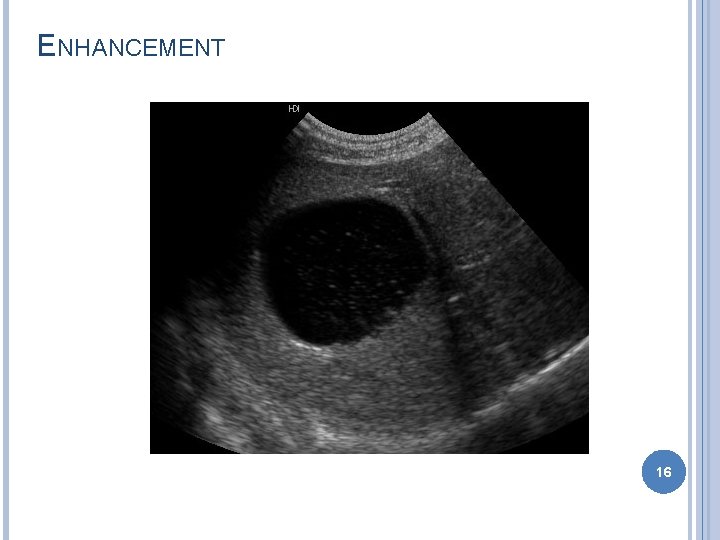

ARTIFACTS Improper machine settings – gain Reverberation � Mirror image – liver GB � Comet tail – gas bubble � Ring down – skin transducer surface Acoustic shadowing Acoustic enhancement Edge enhancement � Border of kidney 11

ENHANCEMENT 16